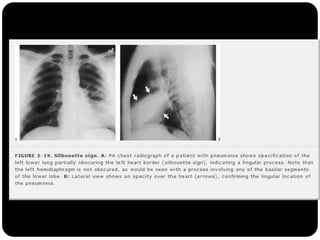

Atelectasia passiva

Sinal da silhueta

Lobo médio: borra o contorno direito do coração.

Língula: borra o contorno esquerdo do coração.

Segmentos basais: borram o contorno do diafragma*** (olhar

imagens anteriores para ver quais).

1. Qual lobo está afetado? Por quê?

É atelectasia?

Lobo

médio(segmento

medial e lateral;

Borra contorno

cardíaco direito

E não é atelectasia!

A fissura horizontal

não está deslocada.

Qual lobo está afetado? Por quê?

Língula pois borra

contorno cardíaco

esquerdo